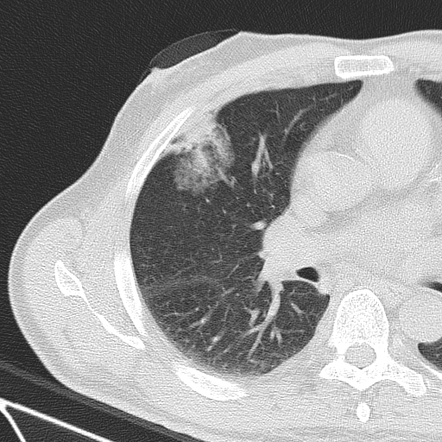

What tool would be the best choice to embolize this pulmonary avm?

vascular plug

Rule 1 of embolics: don’t be dangerous. Clear, large caliber right to left shunt here, so liquids and particles are no good (this is a different scenario than chronic lung disease with bronchial shunting, for which large particles are acceptable). Here, even coils are nerve wracking as they could slip right through, though are definitely an acceptable answer. The vascular plugs are a nice option here as migration risks are lower.